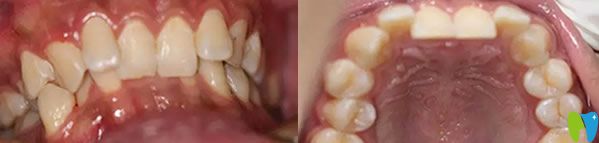

金屬托槽牙齒矯正前:

福州登特口腔牙齒矯正前

恒牙長(zhǎng)上來(lái)后就開(kāi)始擁擠不齊,門牙凹陷,虎牙前突,張嘴笑的時(shí)候總能看見(jiàn)牙齦外露,嘟個(gè)老婆嘴,下前牙輕度擁擠,因?yàn)樯涎赖脑?,?dǎo)致下牙也是內(nèi)凹,吃飯的時(shí)候感覺(jué)總是咬不住食物,咀嚼功能特別差。

來(lái)到福州登特口腔接診的是華醫(yī)生,經(jīng)過(guò)口腔檢查和分析,他建議我做金屬托槽牙齒矯正,不但經(jīng)濟(jì)實(shí)惠而且矯正效果好,這么好的有利條件我當(dāng)然毫不猶豫選擇了金屬托槽矯正。